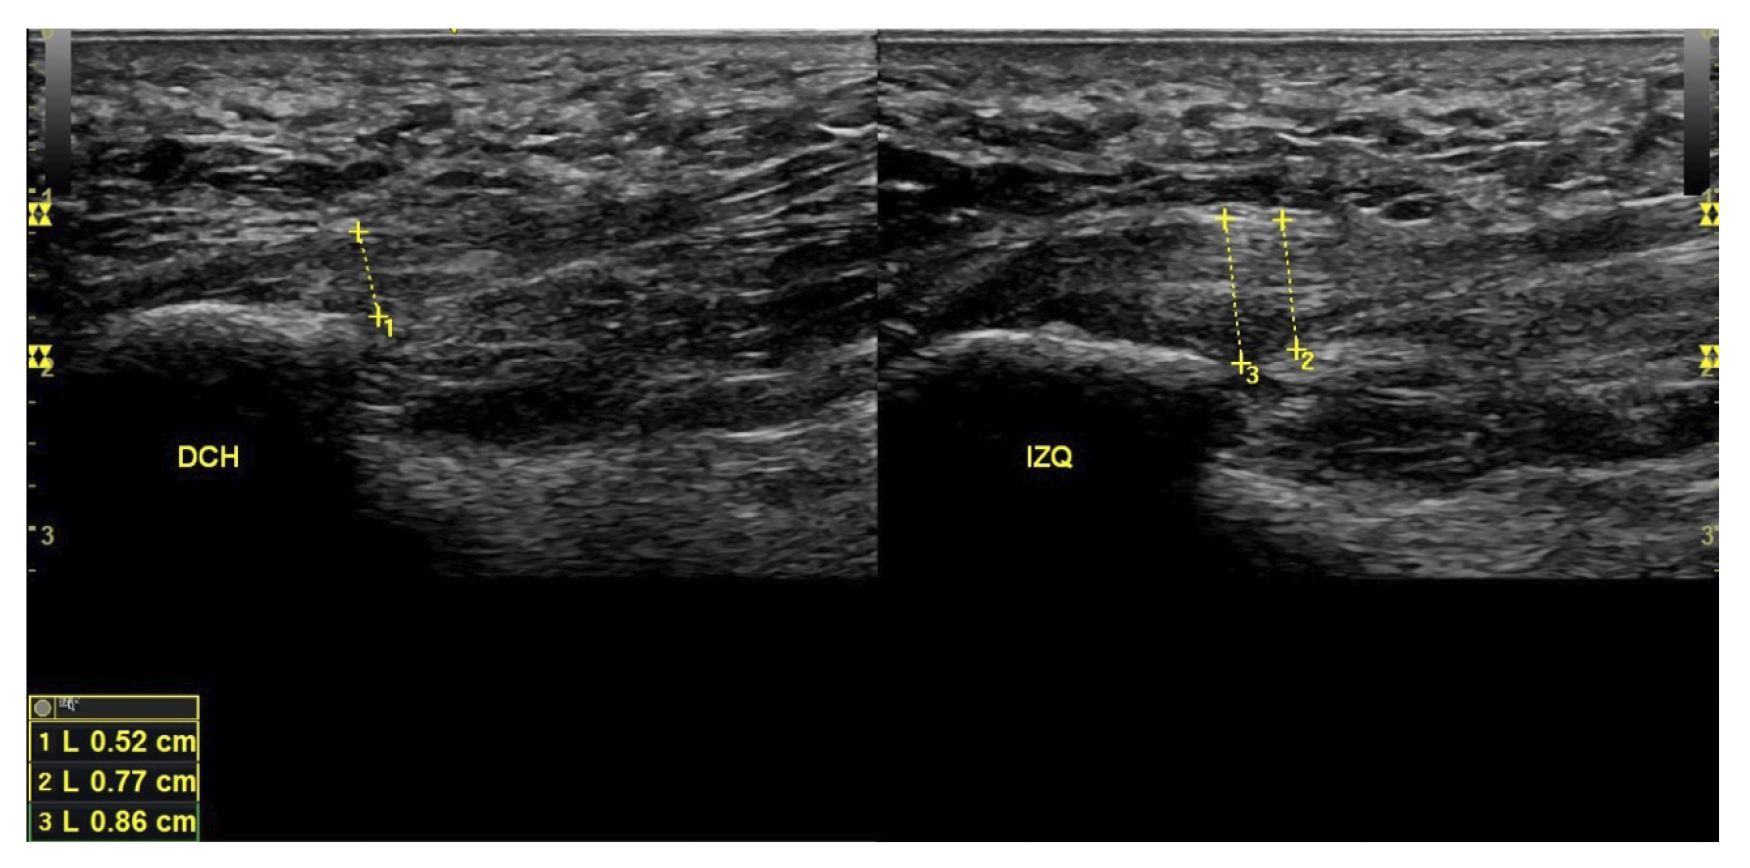

El diagnóstico se estableció en base a los síntomas y se confirmó mediante ecografía con equipo de alta resolución (Alpinion Ecube 9, ALPINION MEDICAL SYSTEMS Co., Ltd., República de Korea) con transductor lineal de 6 a 12 MHz (Figuras 2 y 3).

Figura 3. Área de medición del grosor de la fascia plantar. La línea punteada corresponde con la medición del grosor.